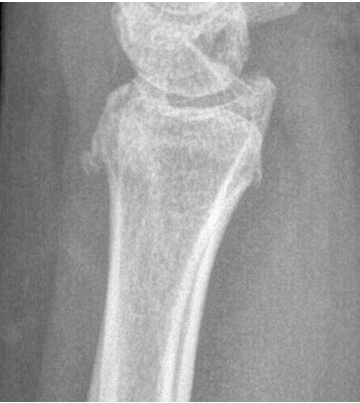

도수 정복 이후 측정한 원위 요골의 영상학적 인자들이 ‘허용 가능한 각도’의 범위일 경우에만 보존적 치료를 시작하였다. 요측 전위 정도는 손목의 전후방 X-ray 사진에서 원위 요골 골편의 요측 이동 정도를 의미한다(Fig. 1). 전후방 전위 정도는 손목의 측방 X-ray 사진에서 원위 요골 골편의 전후방 이동 정도를 의미한다(Fig. 2). 배측 피질골 파절 각도는 원위 요골 골편의 후방 피질골과 요골의 장축이 이루는 각도라고 정의하였다. 배측의 분쇄가 심한 경우에는 단순 방사선 영상에서 가장 뚜렷하게 관찰되는 후방 피질골을 기준으로 각도를 측정하였다(Fig. 3). 수배측 분쇄 골절은 측방 X-ray 사진에서 원위 요골의 수배측에 별개의 골절편(free-floating bony fragment)이 존재하는 경우로 정의하였다(Fig. 4).18) 모든 영상학적 인자들은 도수 정복 전의 초기 단순 방사선 사진 또는 컴퓨터 단층촬영 영상을 토대로 측정되었다. 본 연구는 본원 기관생명윤리위원회(Institutional Review Board, IRB)의 승인(IRB No. 2022-01-013)을 받아 시행한 연구로, IRB에 의해 환자 서면동의서 획득은 면제되었다.

Fig. 4

Lateral radiograph shows a free-floating fragment at the dorsal metaphyseal cortex, indicating dorsal comminution.